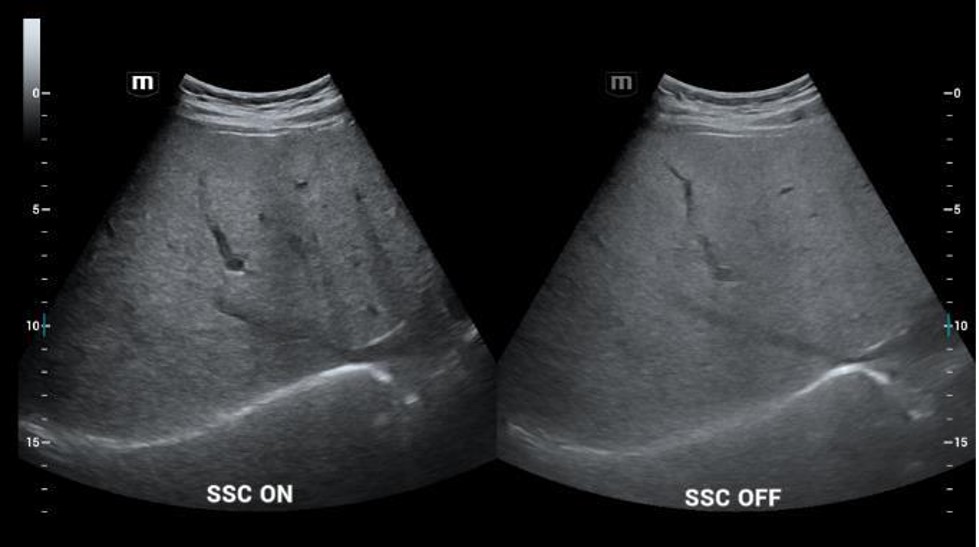

- SSC (Sound Speed Compensation) - rýchlosť zvuku pri USG vyšetrení nastavená štandardne na 1540m/s je pre optimálne zobrazenie automaticky upravená podľa konkrétneho tkaniva človeka 1450 - 1650 m/s

SSC (Sound Speed Compensation): Nastavenie rýchlosti zvuku pri zobrazovaní jednotlivých typov tkanív (obzvlášť užitočné pri diagnostike parenchymatóznych tkanív u ťažkých pacientov). Vylepšené rozlíšenie a penetrácia.

SSC (Sound Speed Compensation): Nastavenie rýchlosti zvuku pri zobrazovaní jednotlivých typov tkanív (obzvlášť užitočné pri diagnostike parenchymatóznych tkanív u ťažkých pacientov). Vylepšené rozlíšenie a penetrácia.